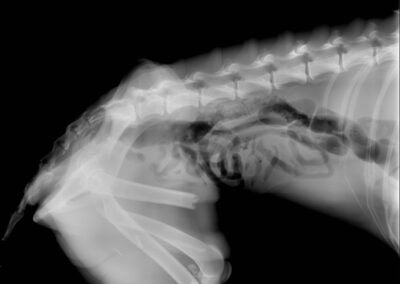

Marcus n’était plus qu’un véritable squelette, avec une fracture complexe du fémur au postérieur gauche. Il a dû vivre un véritable enfer, seul, blessé et affamé…

Il a été opéré en urgence à la clinique du refuge de la FBM, où il est actuellement en convalescence 🩺. La clinique est aujourd’hui totalement saturée, faisant face chaque jour à l’arrivée de nouveaux cas lourds : fractures, blessures graves, chiens brisés par la maltraitance et l’abandon… 😞 Malgré cette situation extrêmement difficile, Marcus a pu être pris en charge et bénéficie désormais de tous les soins nécessaires.